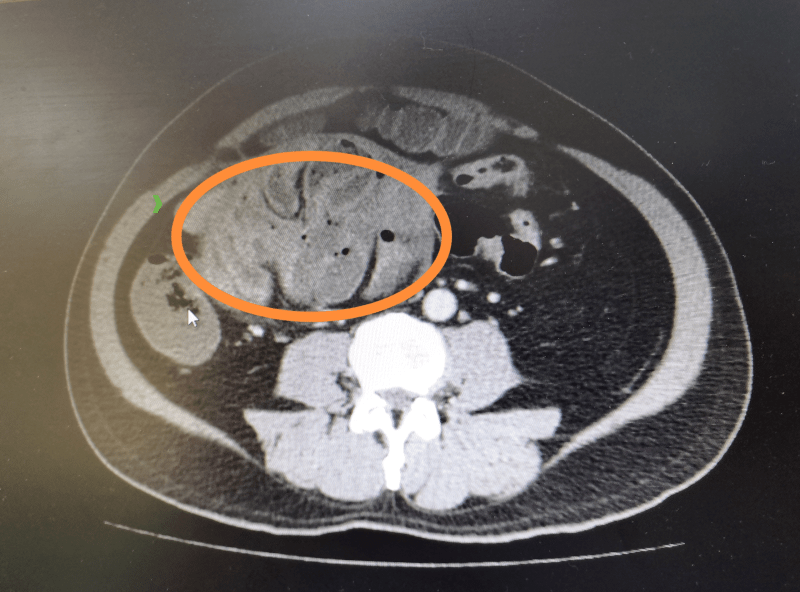

今年59岁的李叔 , 因腹痛伴恶心呕吐5小时到南医三院急诊科就诊 , 据他描述 , 从去年就时而腹痛 , 但情况不严重就没重视 , 也不清楚病因 。 全腹增强CT检查提示:腹内疝 , 十二指肠旁疝可能 。 普通外科医生会诊后 , 建议立即完善相关术前检查 , 安排急诊手术 。

李叔最终被诊断为“急性肠梗阻伴肠坏死;腹茧症” 。 通讯员供图

原来李叔的小肠被“蚕茧”包裹 , 并且广泛地粘连成团 , 肠管张力高、血运差 , 部分肠管还出现了缺血坏死 。 李叔最终被诊断为“急性肠梗阻伴肠坏死;腹茧症” , 随后接受了手术 。